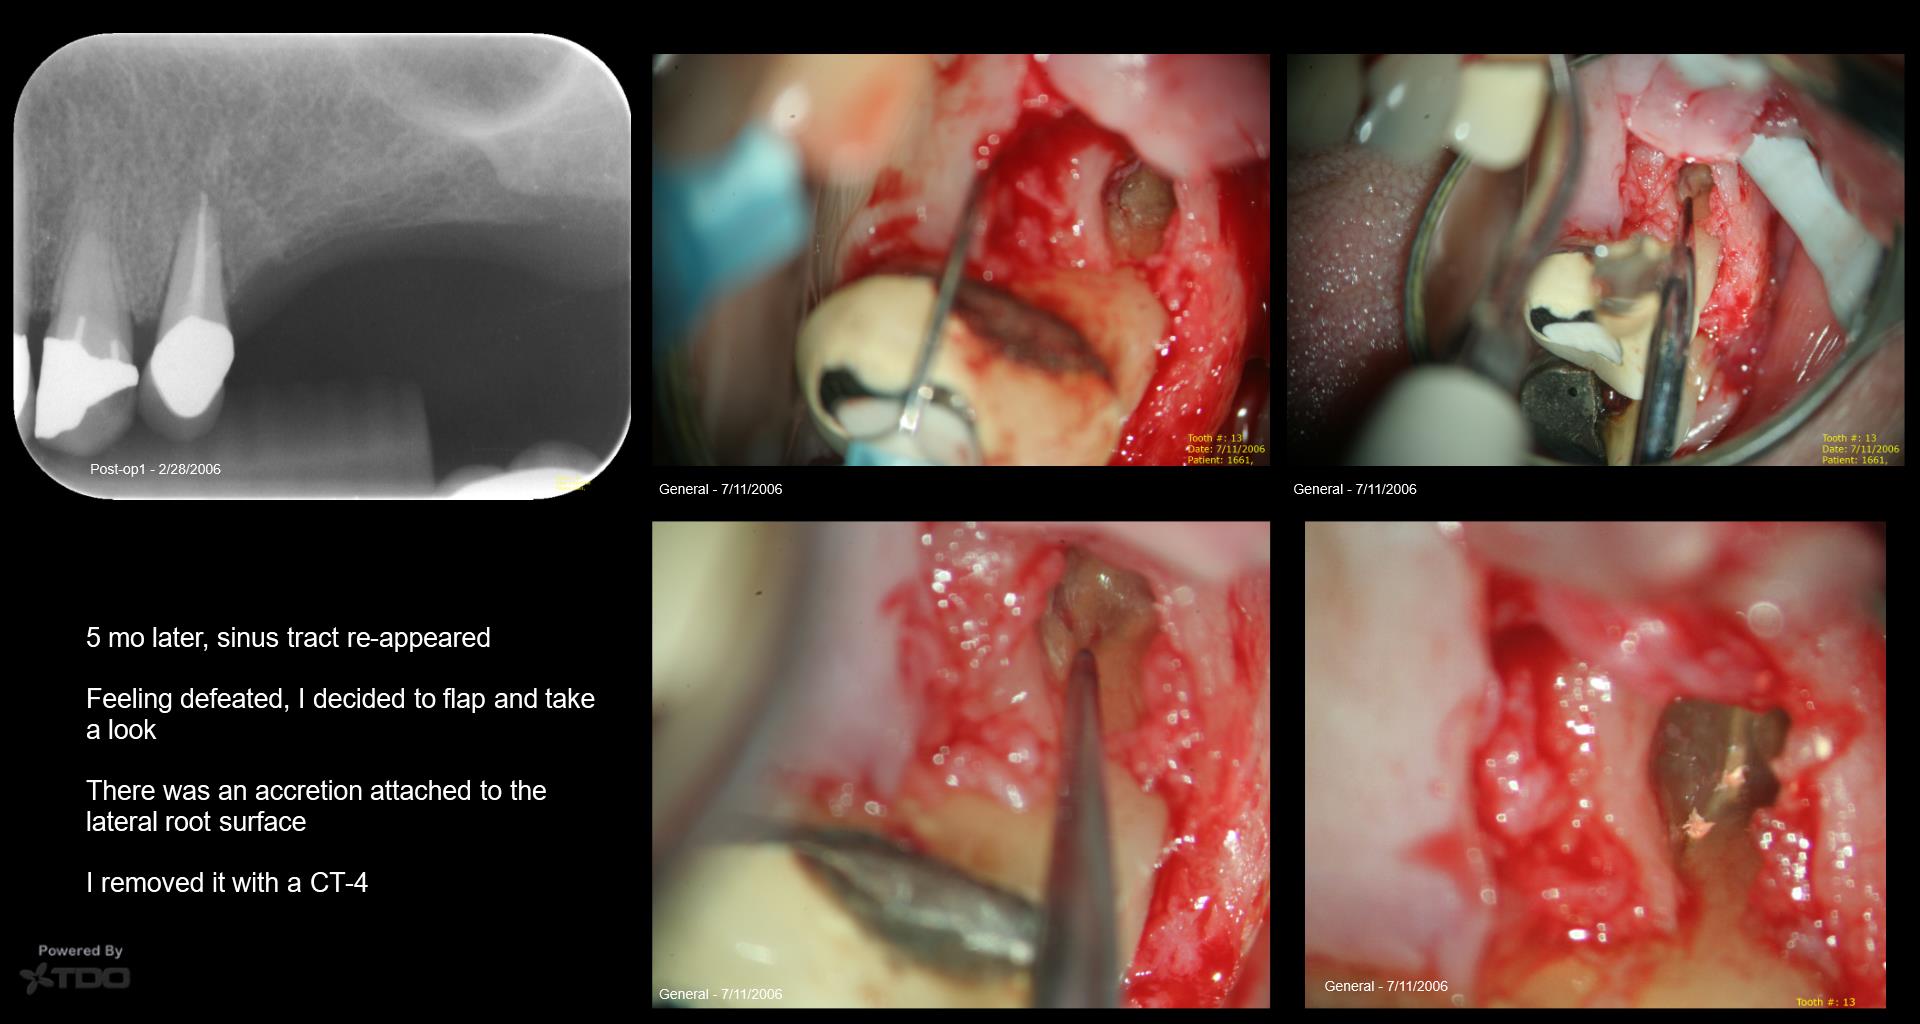

Surprising, indeed! When the sinus tract returned, why not recommend extraction? Also, what is an accretion?